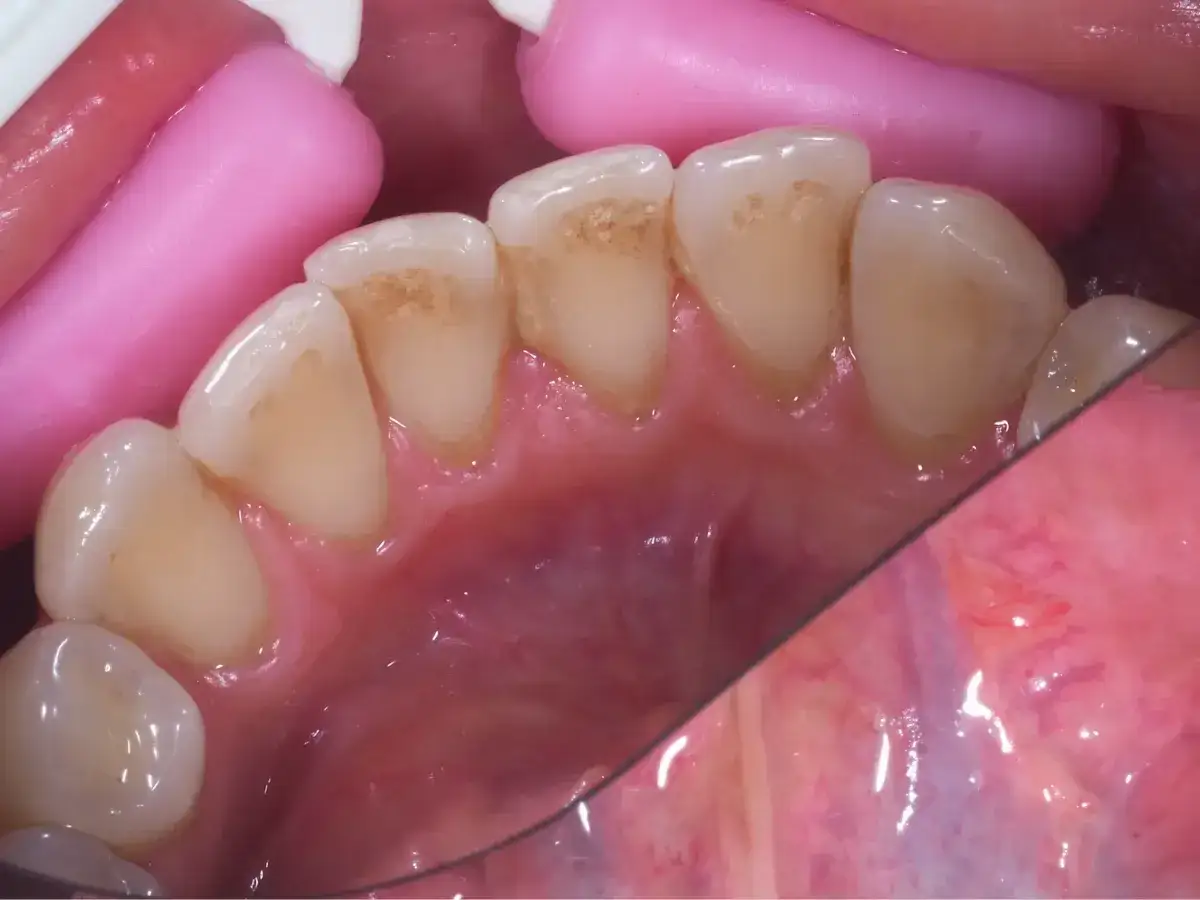

Często spotykanym problemem, szczególnie u dzieci, jest tzw. "black stain", czyli zewnętrzny czarny osad. Charakteryzuje się on ciemnymi kropkami lub liniami, które pojawiają się wzdłuż linii dziąseł, często na zębach mlecznych. Co ciekawe, ten rodzaj osadu jest trudny do usunięcia domowymi sposobami i ma tendencję do nawracania. Chociaż w badaniach bywa opisywany jako zmiana estetyczna i nie zawsze jest bezpośrednio związany z próchnicą, to jednak zawsze wymaga różnicowania z nią. Obecność black stain może wskazywać na specyficzny skład mikroflory jamy ustnej dziecka, a jego usunięcie wymaga profesjonalnego czyszczenia w gabinecie stomatologicznym.

Przebarwienia powierzchowne, takie jak wspomniany wcześniej black stain, mają swoje charakterystyczne cechy. Zazwyczaj pojawiają się jako ciemne kropki, cienkie linie lub paski, najczęściej zlokalizowane wzdłuż linii dziąseł, na zewnętrznych i wewnętrznych powierzchniach zębów. Są twarde i gładkie w dotyku. Co ważne, nie da się ich usunąć zwykłym szczotkowaniem w domu. Nie tworzą one ubytku w strukturze zęba, co oznacza, że szkliwo pod nimi jest zazwyczaj zdrowe. Mimo że są to głównie problemy estetyczne, ich obecność zawsze powinna skłonić do wizyty u dentysty, aby wykluczyć inne, poważniejsze przyczyny.